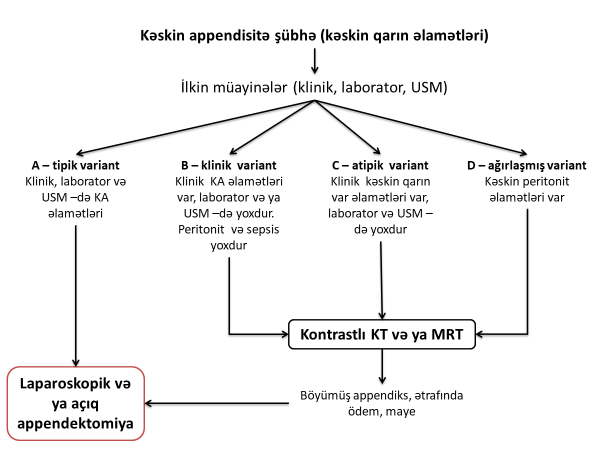

İlkin klinik – laborator – USM nəticələrinə görə bir neçə variant ola bilər (Şəkil 3):

- A variantı – tipik variant, aşağıdakı əlamətlərlə xarkterizə olunur:

- Sağ qalça çuxurunda davamlı ağrı

- Sağ qalça çuxurunun palpator ağrılı olması: hərəkətə bağlı (yerimə, öskürmə, çevrilmə), palpasiya vaxtı ağrı.

- İltihabın ümumi əlamətlərindən ən azı biri – hərarətin artması, leykositoz, qranulositoz, CRP artması.

- Görüntüləmədə digər orqan patologiyası yoxdur.

- Bu vəziyyət kəskin appendisit kimi qəbul edilir və təcili əməliyyat edilir.

- B variantı – klinik variant aşağıdakı əlamətlərə xarakterizə olunur:

- Klinik əlamətlər kəskin appendisiti göstərir, lakin laborator və USM bunu dəstəkləmir və əlavə patologiyanı da göstərmir.

- Bu variant kəskin appendisit kimi qəbul edilə bilər və ya KT (hamilələrdə və uşqalarda MRT) edilə bilər. Belə hala retrosekal appendisitdə, absesdə, infiltratda daha çox rast gəlinir.

- C variantı – atipik variant aşağıdakı əlamətlərlə xarakterizə olnur.

- Klinik əlamətlər tipik deyil, peritonit və sepsis əlamətləri yoxdur. Lakin laborator və USM appendisitə uyğun əlamətləri göstərir. Bu xəstələrdə atipik appendisit və ya digər xəstəliklər ola bilər.

- Bu variantda KT (hamilələrdə və uşqalarda MRT) və ya bir neçə saatlıq dinamik müşahidə aparıla bilər.

- Dinamik müaşahidə ilə kəskin appendisiti inkar etmək mümkün deyilsə, diaqnostik laparoskopiya və ya laparotomiya edilə bilər.

- D variantı – ağırlaşmış variant:

- Klinik əlamətlər tipik deyil, peritonit və sepsis əlamətləri var, USM və laborator əlamətlər qarındaxili iltihabı göstərir. Peritonitin mənbəyini dəqiqləşdirmək məqsədi ilə oral kontrastli KT edilə bilər. Bu xəstələr təcili əməliyyat olunmalıdırlar

Şəkil 3. Kəskin appendisitdə diaqnostik yanaşma